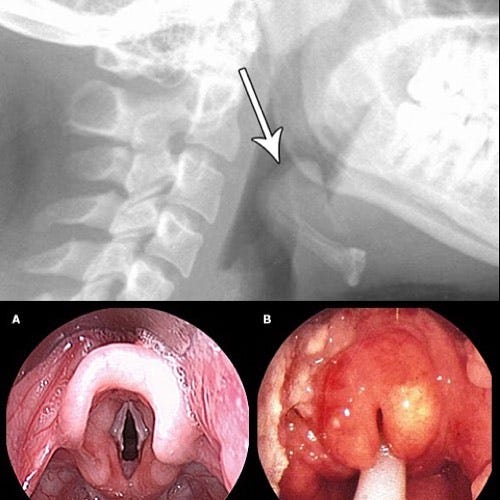

不幸的是,比尔·比克斯比的儿子克里斯托弗患上了会厌炎 ,突然出现呼吸困难,需要进行气管切开术来帮助呼吸,但最终还是在医院去世了。

会厌炎通常是由 b 型流感嗜血杆菌(HiB)引起的。